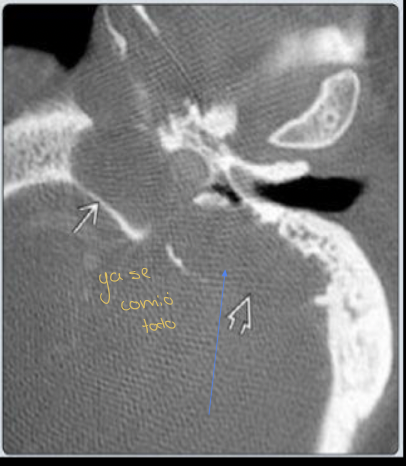

Q

TC Y RM

Pista: Masa que destruye el hueso

Diagnóstico probable